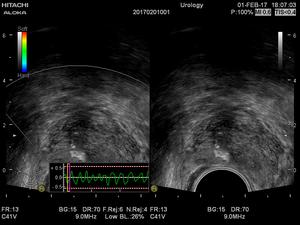

Трансабдоминальное и трансректальное узи простаты с цдк - фото презентация